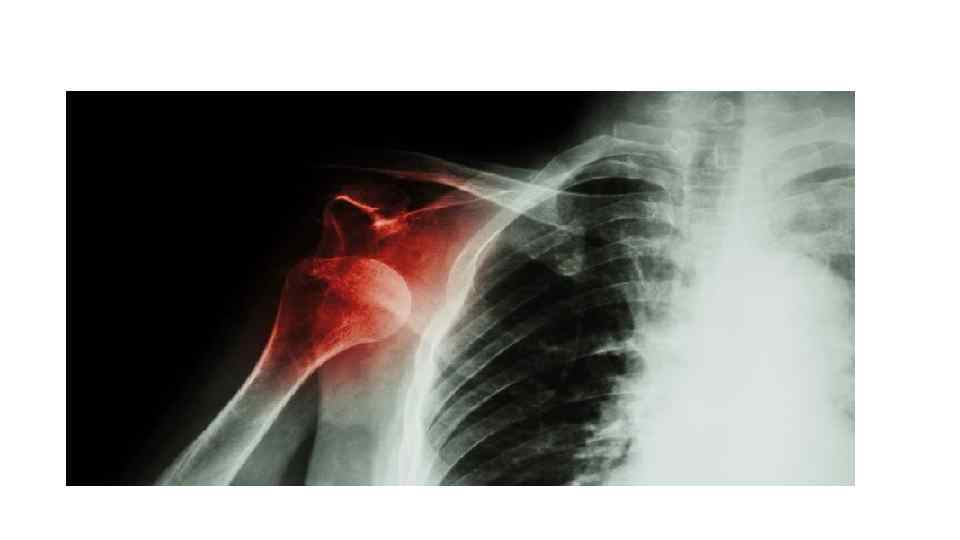

• По степени тяжести различают: • 1) Легкие травмы (растяжения, ушибы). • 2) Средней тяжести (вывих плеча). • 3) Тяжелые (перелом обеих голеней). • 4) Крайне тяжелые травмы (они несовместимы с жизнью).

• Вывих- стойкое разобщение сочленяющихся поверхностей в результате физического насилия или патологического поцесса.

Клиника • Сильная боль • Потеря функции в суставе • Вынужденное положение конечности • Деформация • Sp пружинящего сопротивления (сопротивление пассивным движениям)

Диагностика: RG